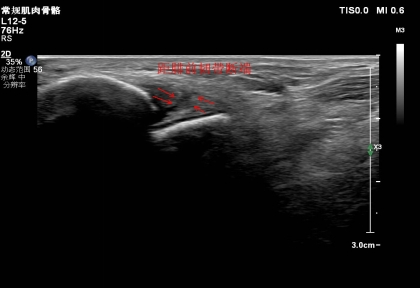

我院超聲科開展肌骨超聲檢查技術

肌骨超聲是指針對肌肉、骨骼、關節及周圍神經的超聲檢查。近年來,隨著超聲技術的不斷發展,肌骨超聲已經被越來越多地用于關節疾病、肌筋膜組織疾病、外周神經病變等疾病的診斷和治療中。

肌骨超聲不僅具備實時動態、價格低廉、無輻射、簡便易行的特點,還可以直觀探查到肌肉骨骼解剖結構和病變,有的放矢地治療相關疾病。

01肌肉及肌腱病變:肌肉及肌腱損傷、肩袖病變、網球肘、高爾夫球肘、跟腱病、足底跖腱膜炎,以及肌腱旁滑囊積液等。

02韌帶病變:腳扭傷后踝關節外側距腓前韌帶損傷、跟腓韌帶損傷、膝關節內、外側副韌帶病變等。

03骨與軟骨?。簨雰后y關節發育不良的篩查(DDH)、肋骨骨折、部分骨腫瘤等。

04關節病變:檢測類風濕關節炎(rheumatoidarthritis,RA)滑膜炎、肌腱/腱鞘炎和骨侵蝕等病變,以及銀屑病關節炎,痛風性關節炎。

05神經病變:神經卡壓癥、神經脫位、神經腫瘤、解剖變異和創傷等。